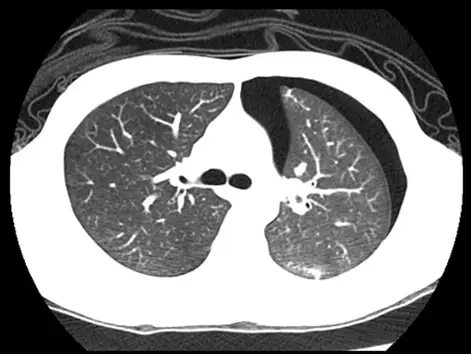

男性患者突然左胸痛,未施打顯影劑的胸腔電腦斷層在左肺旁發現異常(如下圖所示),最適當的診斷為何?

- 影像切面與窗位:這是一張非顯影劑注射的胸部電腦斷層(Non-contrast Chest CT)軸切面(Axial view)影像。影像採用「肺窗(Lung window)」設定,主要用於觀察肺實質(Lung parenchyma)與含氣構造。

- 異常發現:在左側胸腔(圖片右側,依放射學慣例)的肋膜腔內,可見一呈現新月形(Crescent-shaped)的「極低密度區(Hypodense area)」,其密度與體外空氣相當(CT值接近 -1000 HU),且呈現全黑狀態。

- 關鍵特徵:該極低密度區域內「完全沒有肺紋理(Lung markings)」(即無微血管、支氣管等構造)。

- 邊界特徵:在正常充氣的左肺實質與該無肺紋的黑色區域交界處,可以清晰看見一條細白的「臟層肋膜線(Visceral pleural line)」。左肺因受到外側空氣的壓迫,呈現部分塌陷(Collapse)且向內側退縮。這些徵象是氣胸(Pneumothorax)極為典型且明確的影像學表徵。

- (A) 氣胸(Pneumothorax):正確。影像中左側肋膜腔內出現極低密度(空氣密度)且無肺紋理的空間,加上臟層肋膜線的顯現與肺臟的部分塌陷,與男性患者「突發性單側胸痛」的臨床症狀(常見於自發性氣胸)完全吻合。

綜合上述影像分析,患者左側胸腔內存在一大片沒有肺紋理的空氣密度區,並可見明顯的臟層肋膜線與受壓迫的肺組織,這明確指出肋膜腔內有不正常的空氣蓄積。配合年輕男性「突然左胸痛」的典型自發性氣胸(Spontaneous pneumothorax)臨床表現,影像學上呈現極低密度且無肺紋理的特徵,故最適當的診斷為 (A) 氣胸。血胸與乳糜胸皆屬液體積聚,CT 密度表現與本圖完全不符;連枷胸則為胸壁骨骼損傷的特有表現,非單純的肋膜腔異常。

- 氣胸的典型影像徵象:肋膜腔內出現無肺紋理的極低密度區(空氣)、清楚可見的邊界線(臟層肋膜線,Visceral pleural line)、受壓迫塌陷的肺組織。